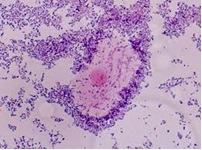

Soi tươi bệnh phẩm dịch âm đạo

nhận định nấm và Trichomonas vaginalis

Trichomonas vaginalis